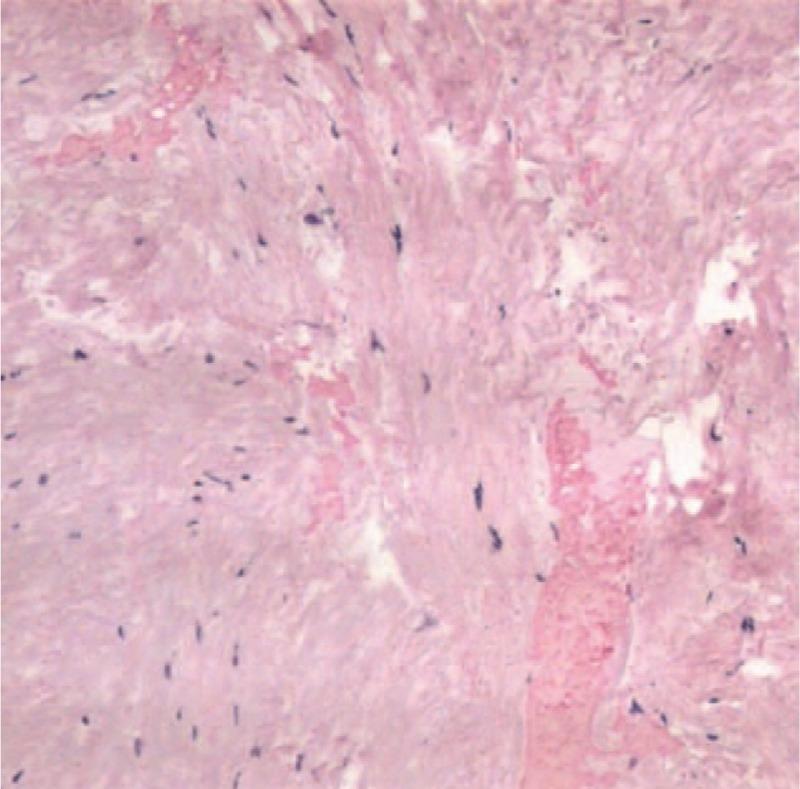

An abnormal ligamentum flavum was observed intraoperatively. A histological examination revealed extravasation of blood in the degenerated ligamentum flavum. Postoperatively, the lower limb pain improved immediately. At the 6-month follow-up, the pain and numbness of the lower limb disappeared, and the muscle strength of both legs recovered completely with normal gait.

术中观察到黄韧带异常。组织学检查显示退变的黄韧带内有血液外渗。术后,下肢疼痛立即改善。在6个月的随访中,下肢疼痛和麻木消失,双腿肌力完全恢复,步态正常。